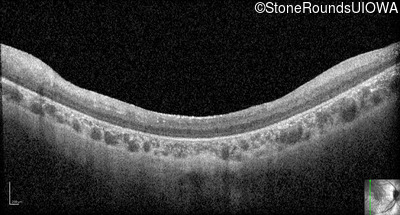

Optical Coherence Tomography - Left - 20/500 sc

Exemplar / OCT Stack